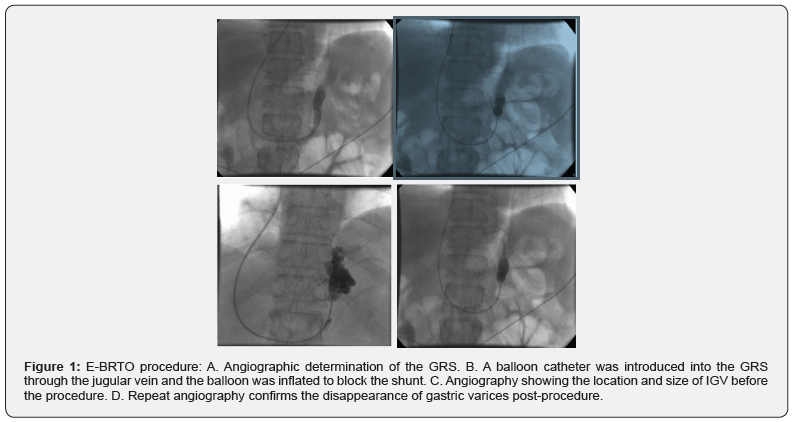

In this retrospective study, the data for patients that had IGV with or without EV and GRS and underwent E-BRTO between January 2016 and July 2019 at our center was collected. All patients provided informed consent prior to the treatment. The study was approved by the Institutional Review Board of the Fifth Medical Center of PLA General Hospital in Beijing. Upper gastrointestinal endoscopy was performed to assess the severity of IGV. Contrastenhanced Computed Tomography and Venography (CTV) of the portal venous system was performed to visualize the feeding and draining veins of the IGV (Figure 1A).

A 5.5F balloon occlusive catheter was introduced into the hepatic vein through the right internal jugular vein or the right femoral vein. The wedge pressure of the hepatic vein was measured after balloon occlusion of the hepatic vein. The free pressure of the hepatic vein and the inferior vena cava pressure were measured after removal of the occlusion. Finally, the Hepatic Vein Pressure Gradient (HVPG) was calculated. Angiography was performed to visualize the prominent GRS and IGV (Figure 1B). According to the diameter of GRS, a balloon catheter with appropriate size was selected to block the GRS. The balloon occlusive catheter was introduced into the shunt and inflated to occlude the GRS (Figure 1C). Repeat angiography was performed to evaluate the position and size of the IGV (Figure 1D). The patient was placed in a left lateral position and the vital parameters of the patient (including heart rate, respiratory rate, oxygen saturation, and blood pressure) and electrocardiogram were continuously monitored preoperatively. Endoscopic examination was conducted to confirm the presence of GV and the volume of the varices (Figure 2A). Histoacryl was injected into the GV at multiple points. Each injection was performed with the “sandwich technique” i.e. 1.5mL Histoacryl was sandwiched between two doses of 2mL 50% glucose solution depending on the volume of the needle (Figure 2B). After each injection location, a satisfactory result was defined as hardening of the varices on gentle probing of the varices using a needle catheter. At the end of the procedure, before removing the balloon catheter, a repeat angiogram was performed to confirm the resolution of the IGV (Figure 1D). The therapy was defined as successful if the blood supply of the IGV was completely obliterated. The balloon occlusive catheter was then deflated and removed.